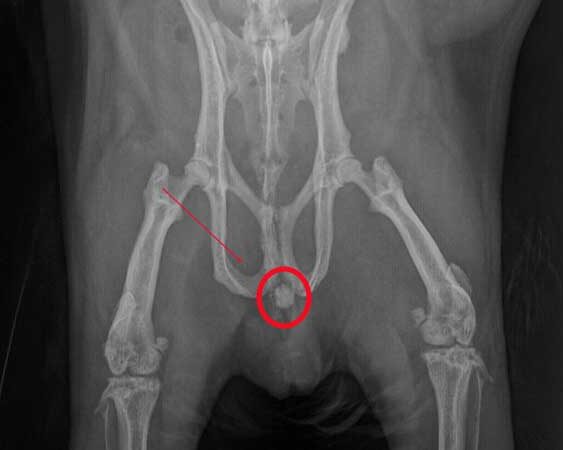

Nach Röntgenaufnahmen war schnell klar: Ein großer Harnstein hatte sich im Bereich des Beckens festgesetzt. Der zusätzliche Ultraschall zeigte freie Flüssigkeit im Bauchraum. Das ist ein Hinweis auf eine mögliche Harnblasenruptur. Kann der Urin nicht mehr abfließen, besteht im schlimmsten Fall die Gefahr, dass die Blase reißt. Der Harn kann sich aber auch bis in die Nieren zurückstauen und zum Nierenversagen führen. Es musste also schnell gehandelt werden.

Bei Stöpsel war der Harnstein ziemlich groß, fast einen halben Zentimeter, und in einer äußerst ungünstigen Position in der Harnröhre verkeilt. Er war nicht mehr in der Blase, aber auch noch nicht in der Nähe der Penisspitze, wo man ihn hätte leichter entfernen können. Eine Operation war bei dieser Lage nicht möglich. Judith Führers Ziel war es also, den Stein zunächst vorsichtig mit einem Katheter in die Blase zurück zu spülen. Das birgt bei männlichen Meerschweinchen zusätzlich Schwierigkeiten, denn sie haben zwei Öffnungen am Penis, man muss also sehr genau wissen, wohin man den Katheter führt.